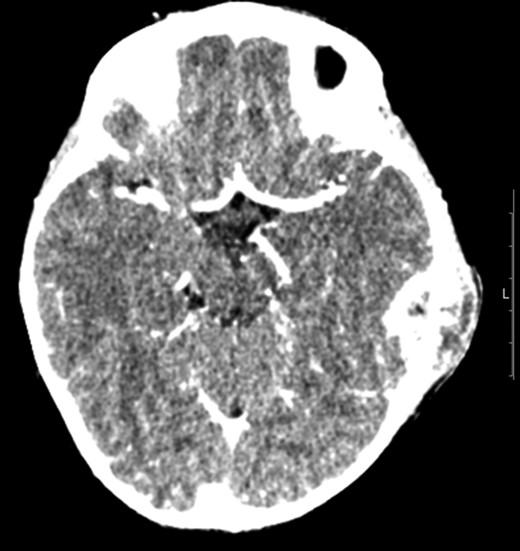

Otogenic TB was first described by Jean Loius Petit [4]. Records from the early 20th century report an incidence of TB otitis media of 2.8% in the paediatric population by Fraser et al. (1915) [4]. The landscape has changed immensely since this time in line with the general reduction in TB associated with immunization programmes and socioeconomic factors such as improved housing [1]. Most sources are now associated with overseas contacts but even in TB endemic countries the occurrence of paediatric otogenic TB is rare with only a few paediatric case reports presented in literature (Fig. 4). Intracranial complications of otomastoiditis is even rarer and include meningitis, encephalitis, empyema, extradural collections and sinus venous thrombosis [5], which makes the management of such cases extremely challenging. And out of paediatric case reports presented, only one was found to have reported intracranial complications [6].

Literature overview of paediatric otomastoiditis case reports from 1980 onwards searched through OVID Medline and Embase databases and references of searched case reports. (With exclusion of non-English language-based case reports.)